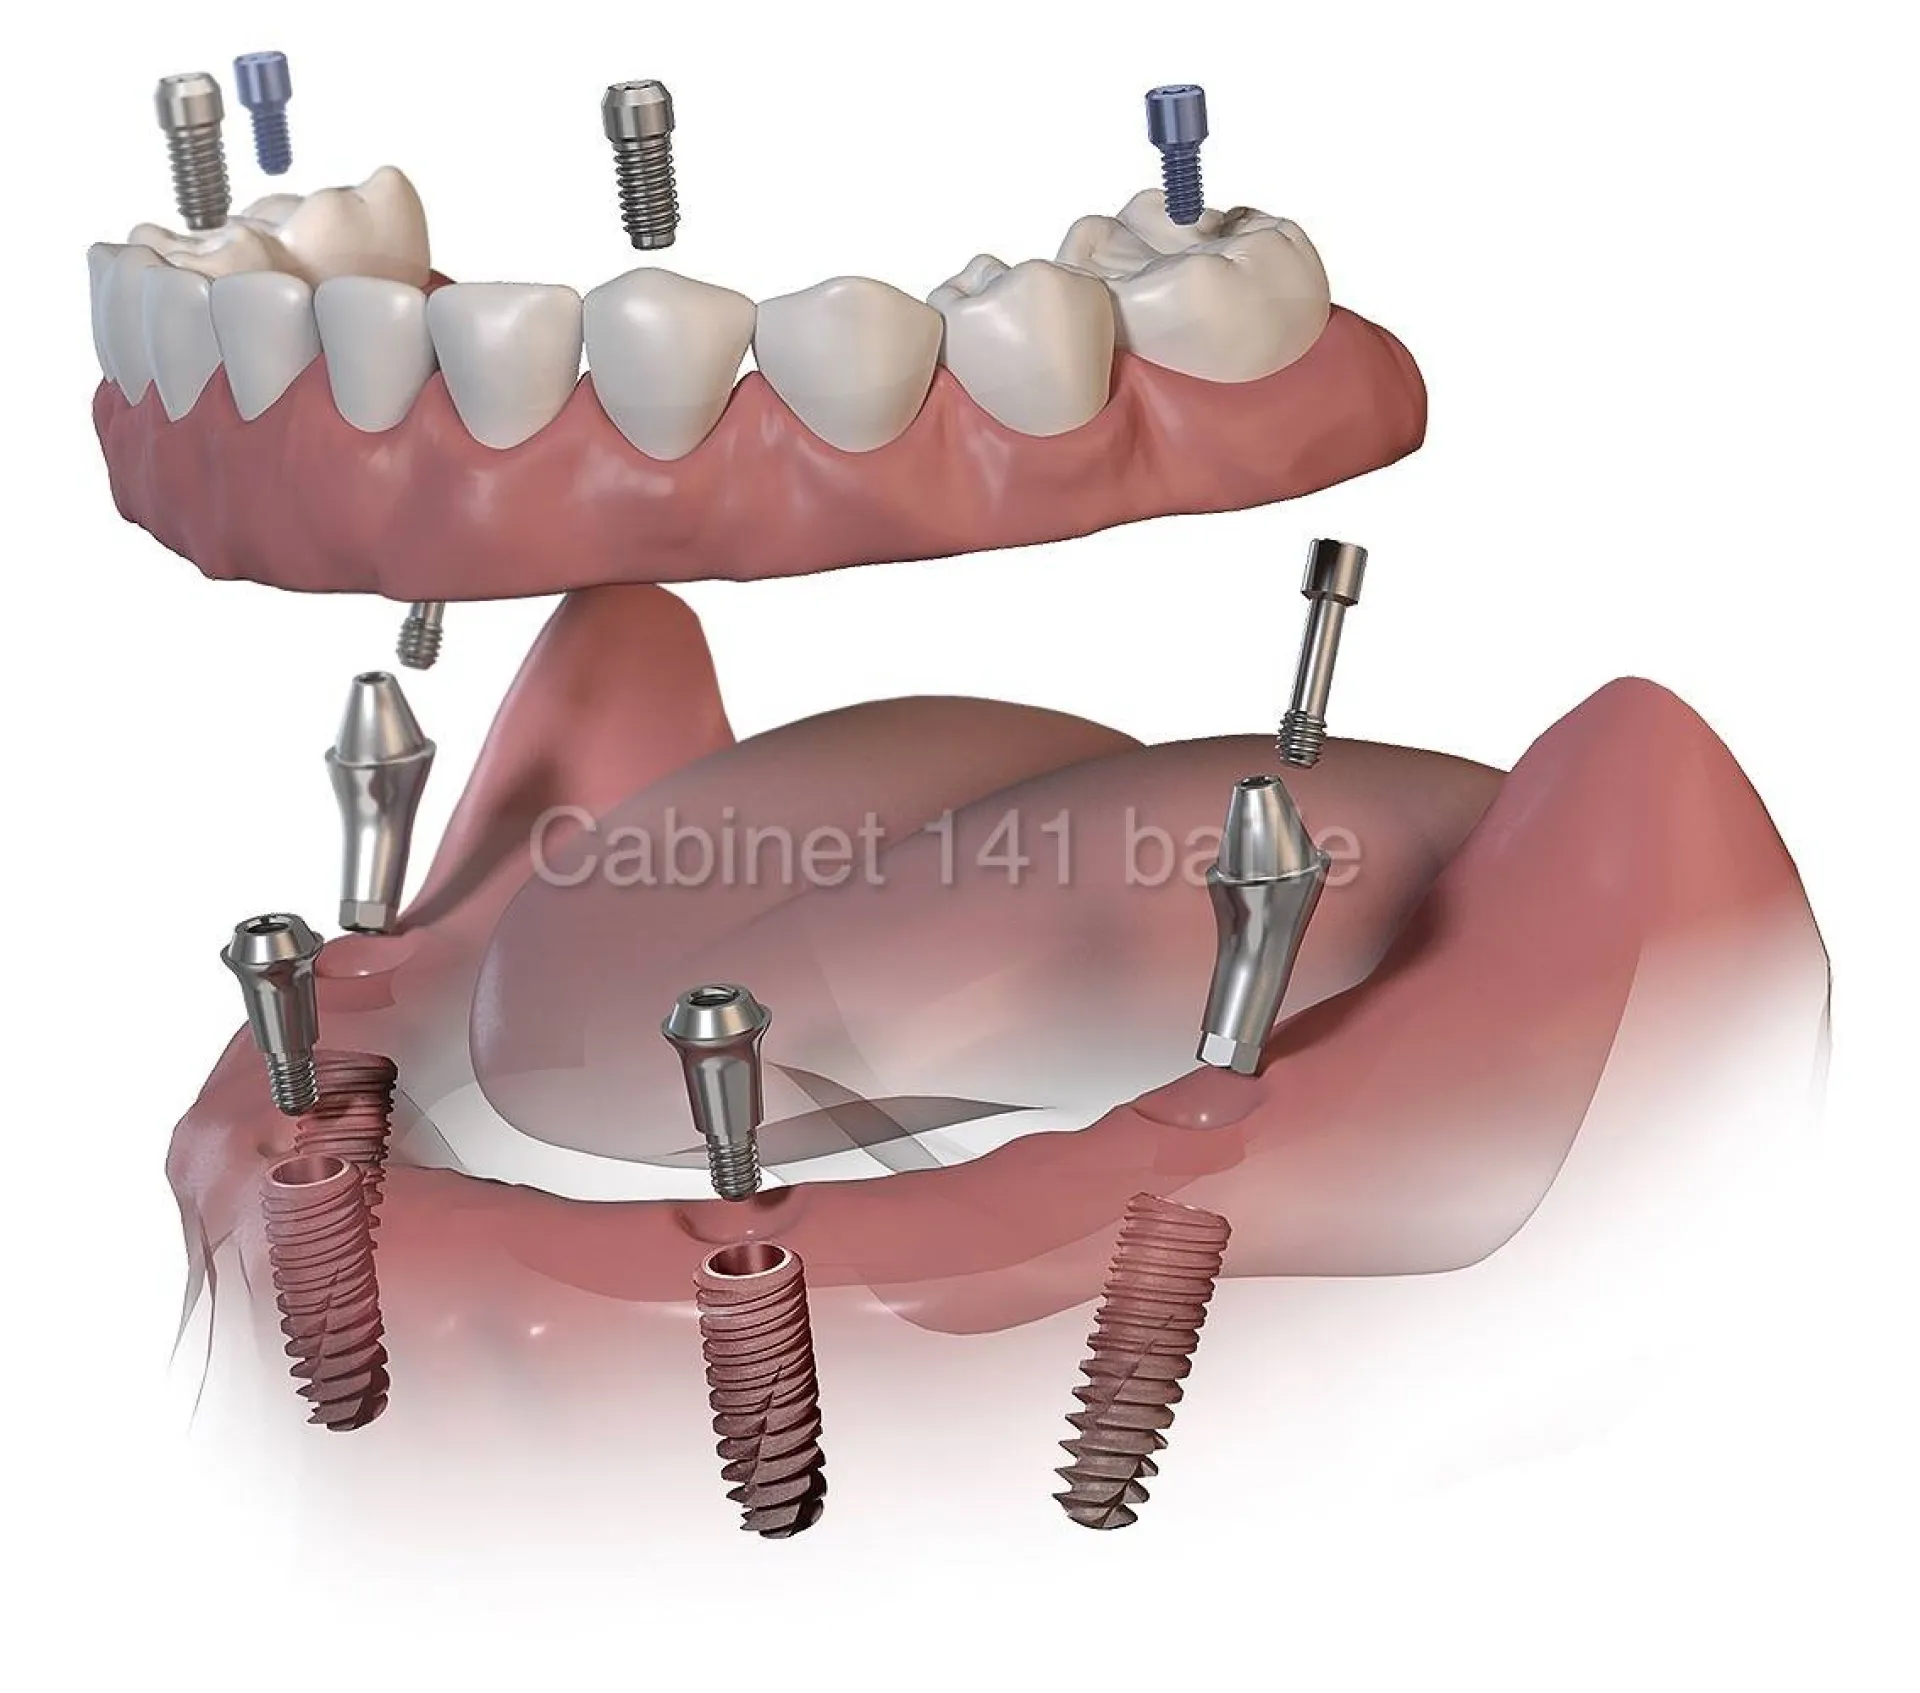

La Technique All-on-4® (Tous sur 4) : Cette méthode révolutionnaire permet de poser une arcade dentaire complète sur seulement 4 implants judicieusement positionnés. Elle est souvent la solution idéale en cas de perte osseuse, évitant ainsi des greffes osseuses complexes.

La Technique All-on-6® (Tous sur 6) : Pour une stabilité et une durabilité encore accrues, notamment pour les mâchoires offrant un bon volume osseux, 6 implants peuvent être posés pour soutenir le bridge fixe.

La technique All-on-4® (Tous sur 4) : Comme son nom l'indique, cette procédure repose sur la pose de seulement 4 implants dentaires par arcade, positionnés stratégiquement pour offrir un support maximal. Les deux implants antérieurs sont droits, tandis que les deux postérieurs sont inclinés pour exploiter l’os disponible sans recourir systématiquement à une greffe osseuse.

La technique All-on-6 (Tous sur 6) : Cette approche utilise 6 implants par arcade pour une assise encore plus large et une force de mastication optimisée. Elle est souvent recommandée lorsque la qualité et la quantité osseuse le permettent, offrant une robustesse supplémentaire.